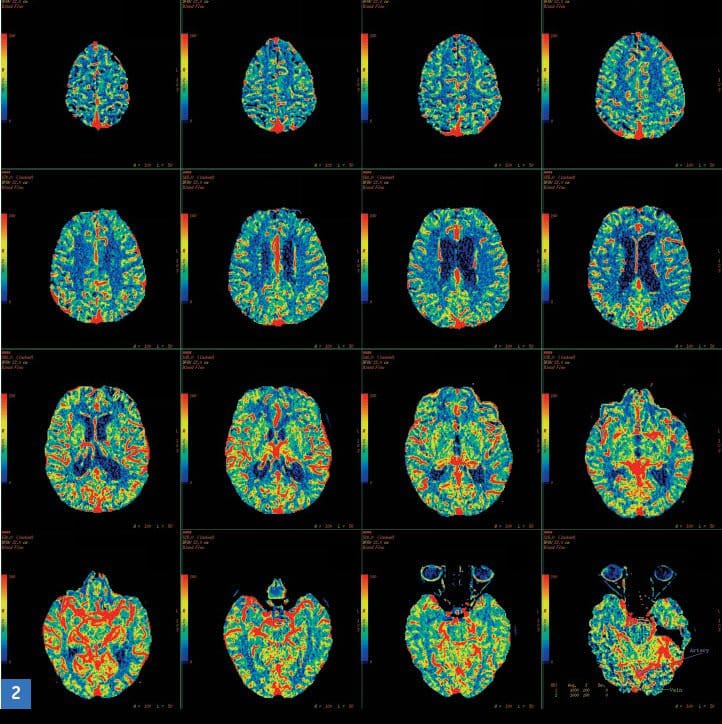

Per ovviare a tale problema, l’equipe della Di Paola ha reclutato diversi volontari, suddividendoli per severità di patologia ed esaminandoli tramite Voxel Based Morphometry e il

Diffusion Tensor Imaging. Tali tecniche hanno evidenziato due distinti processi di degenerazione della sostanza bianca del corpo calloso, individuando dove e come questo subisce cambiamenti

durante il corso della malattia.

Allora, secondo i ricercatori la conoscenza acquisita permetterà di osservare il corpo calloso come biomarker dei cambiamenti provocati dalle varie fasi dell’Alzheimer: dalla fase

preclinica (la Mci) a quella di demenza di grado lieve, fino a quella di grado più severo.